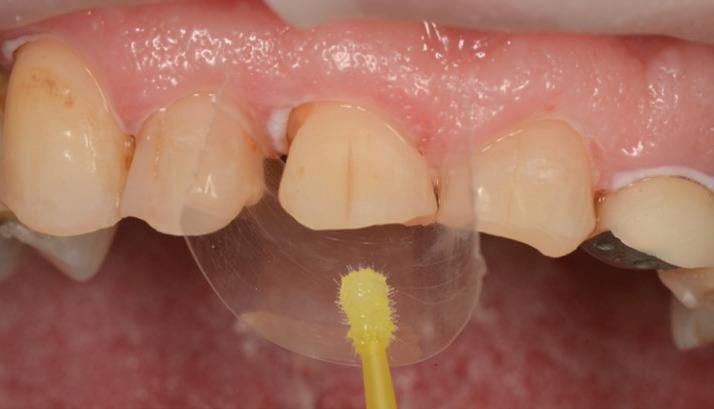

The maxillary anteriors were then isolated one at a time, and a selective etch adhesive protocol was used with the adhesive OptiBond™ Universal by KerrTM (Fig. 8).

Flowable composite (HerculiteTM Ultra Flow, Shade A2) was then applied to the dentine surface and cured, to complete the adhesion process (Fig. 9). The tooth was then restored with a new nanohybrid composite material, HarmonizeTM by KerrTM